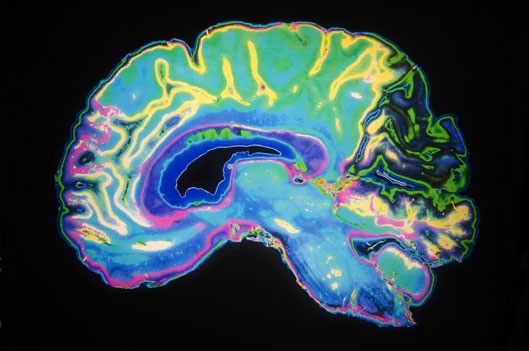

Gene Wilder’s death on Aug. 29 at age 83 from complications of Alzheimer’s disease prompted tributes across generations of fans of the beloved comic actor. It also focused additional public attention on Alzheimer’s, a progressive neurological disease that is the leading cause of dementia.

The doctors say that people usually begin showing signs — such as misplacing items, having difficulty keeping track of events, or repeating questions — five to 10 years before they’re diagnosed. The changes in the brain caused by the disease may begin occurring decades before symptoms even appear.

“Those changes start happening for most of us in the midlife period,” Shah says, “Our brains are so resilient that it protects itself, and it takes a long time before Alzheimer’s becomes symptomatic.”